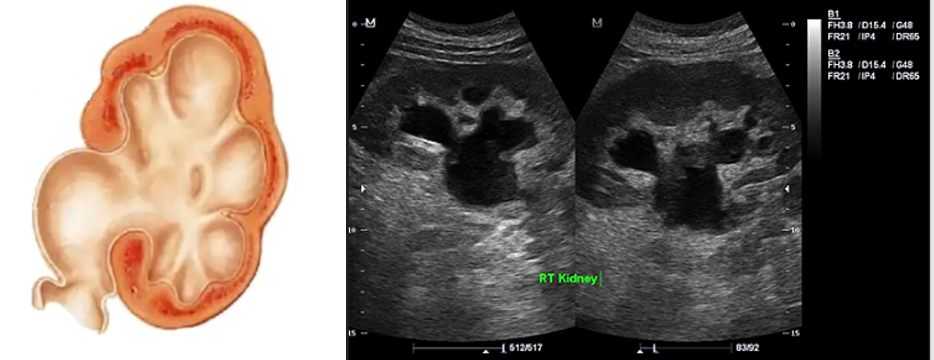

Врожденный гидронефроз

• Гидронефроз (гидронефротическая трансформация) - стойкое, прогрессирующее расширение коллекторной системы почки вследствие нарушения оттока мочи на уровне лоханочно-мочеточникового сегмента, сопровождающееся атрофией паренхимы почки вплоть до её полной гибели.

Различают 3 стадии гидронефроза (Лопаткин Н.А., 1988):

• 1 стадия – Расширение только лоханки (пиелоэктазия) с небольшим нарушением почечной функции.

• 2 стадия – Расширение не только лоханки, но и чашек (гидрокаликоз с уменьшением толщины паренхимы почки и значительным нарушением её функции).

• 3 стадия - Резкая атрофия паренхимы почки, превращение её в тонкостенный мешок.

При УЗИ:

• Значительное стойкое расширение чашечно-лоханочной системы почек в зависимости от стадии гидронефроза.

• Постепенное истончение почечной паренхимы вплоть до полной атрофии.